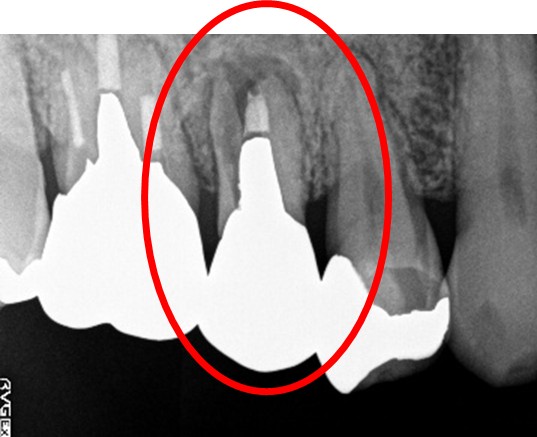

ブリッジの支台になっている奥の歯が、被せ物の中で虫歯になり、支台の役割を果たさず、前方の歯のみで支えられていました。前方の歯をそのままにして、後方の部分を切り離すと、そのまま取れてきました。中は、虫歯で歯根しか残っていない状況でした。この歯は、根管治療後、単独でオールセラミック冠を被せ、歯のないところにインプラントを埋入しました。

冠の中で大きな虫歯になり支台の役割を果たしていませんでした。

【インプラント埋入前】

冠はブリッジを切断しただけで取れてきました。軟化象牙質を取り除いたところ、歯根しか残っていない状況で保存できるかどうかのぎりぎりのところでした。